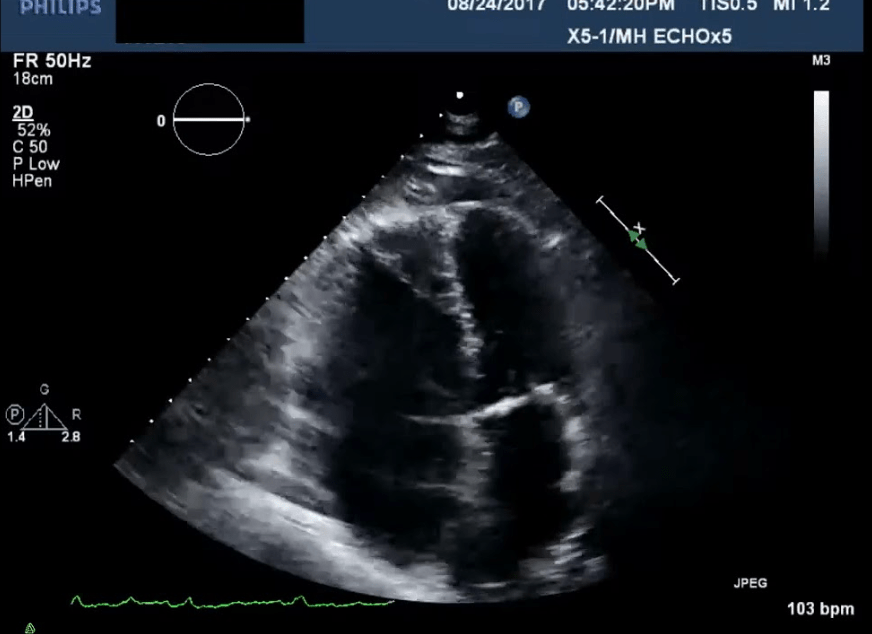

A 62-year-old man, postoperative day 3 after hip surgery, suddenly develops acute dyspnea and chest pain.

On arrival of the rapid response team: HR 132 bpm, BP 78/46 mmHg, RR 32, SpO₂ 86% on non-rebreather currently on distress. Exam reveals distended neck veins and cool extremities. Labs with elevated Troponins and Pro-BNP for the age.

POCUS reveals this:

What is the most appropriate immediate treatment?

Thrombolysis with alteplase (tPA)